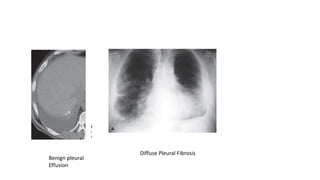

Benign pleural

Effusion

Diffuse Pleural Fibrosis

• Diffuse pleural thickening and diffuse pleural fibrosis are thought to

develop after a previous asbestos-related pleural effusion, involve the

visceral pleura, and affect the pleural surface adjacent to the costophrenic

angle, a distinguishing feature from pleural plaques.